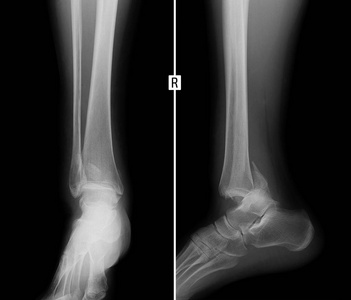

右下腿骨折 病態

1 被害者の属性 代・女性・会社員 2 事故の態様 自動車が故障したために、自動車の後部に立っていたところ、スリップした自動車が衝突してきた事案 3 傷害の態様 右下腿骨折自体は手術により、骨癒合されました。しかし、右膝付近に痛みが残り、また、正座ができない、階段を下りる際に図1.右下腿x線検査二脛骨・腓骨骨折を認めた. 図3.創外固定術後 め,挫創と骨折部が一致するため開放骨折と考え られた.創より血液が噴出したことから血管損傷 を疑い造影ct検査(図2)を施行永久保存版膝の痛み部位別まとめ 1.大腿骨顆上骨折について 大腿骨の遠位部(膝関節の上部)の骨折をいいます。 主に車やバイクでの事故やスポーツなどでの強力な衝撃により受傷します。 骨粗鬆症のある高齢者では、正座のような形で転倒すると受傷することもあります。